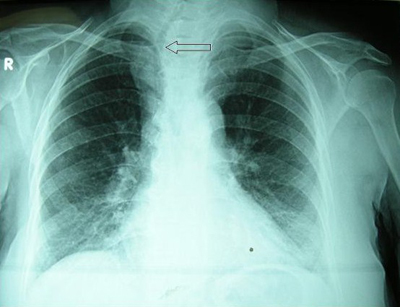

Tanıda öncelikle substernal guatr olasılığından şüphelenmek önemlidir. Boyunda guatr tespit edilen hastalarda muayenede palpasyon çok önemlidir. Palpasyonda yutkunma esnasında ve boyun ekstansiyonunda guatr alt sınırı palpe edilemiyorsa ve sternoklaviküler bölgede kitle devamlılık gösteriyorsa substernal guatrdan şüphelenilmelidir. Tanıda valsalva manevrası kullanılabilir.[22] Ancak büyük substernal guatrların %20'sinden fazlasının boyundan palpe edilemeyebileceği unutulmamalıdır.[14] Substernal guatrdan şüphelenilen olgularda direk radyografide üst mediastende radyoopasite ve trakeal itilme görülebilir (Resim 1). Hastaların yaklaşık %61'inde direk grafide trakeada itilme mevcuttur.[13] İçerisinde kalsifikasyon olan guatrlarda mediastende kalsifiye lezyon izlenebilir. Ultrasonografi boyundaki kısımla ilgili bilgi verebilir ancak substernal uzanımı göstermede yetersiz kalır. Sintigrafik incelemeler bazı tiroid lezyonları radyoaktif iyodu tutamadıklarından az oranda fayda sağlar. Bu sebeple ender olarak kullanılmaktadır.[14] Bilgisayarlı tomografi, guatrın uzanımını ve komşu yapılara yakınlığını çok iyi gösterdiği için tanıda altın standarttır (Resim 2). Damarsal yapılara yakınlığı göstermek için kontrastlı tomografi tercih edilebilir. Tiroid hacmini belirlemek amacıyla üç boyut rekonstrüksiyonlu spiral tomografi yapılabilir.[23] Manyetik rezonans görüntüleme komşu yumuşak dokularla olan ilişkiyi göstermede yardımcı olabilir. İnce iğne aspirasyon biyopsisi yapılabilir ancak mediastene uzanan bölümden alınması zordur. Bu sebeple mediastene uzanan kısımdan aspirasyon biyopsisi önerilmemektedir.[14] Substernal guatrlarda malignite riski literatürde %6 ile 21 arasında değişmektedir.[13] Mathew ve ark. 2008 yılında yaptıkları metaanalizde de benzer oranlar bulmuş ancak incelediği bir grup çalışmada boyundaki guatrlara göre daha yüksek malignite riski olmadığını vurgulamıştır.[2] Ailede tiroid hastalığı öyküsü, boyuna radyoterapi uygulanması veya radyasyona maruz kalma, tekrarlayan guatr ve boyunda lenfadenopati varlığı malignite olasılığını artıran faktörlerdir.[2]

Resim 1: Ön-arka akciğer grafisinde substernal guatra bağlı trakeada sağa itilme (ok işareti) |